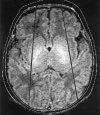

Background and purpose: Analysis of specific features in the brain of patients with holoprosencephaly (HPE) may clarify normal and abnormal brain development and help predict outcomes for specific children. We assessed sulcal and gyral patterns of cerebral cortex in patients with HPE and developed a method of grading brain development.

Methods: Neuroimaging studies (75 MR imaging, 21 CT) of 96 patients with HPE were retrospectively reviewed, with specific attention paid to the cerebral cortex. Thickness of cortex, width of gyri, and depth of sulci were assessed subjectively and by measurement. The angle between lines drawn tangential to the sylvian fissures ("sylvian angle") was measured in each patient with HPE and in 20 control patients.

Results: Thickness of cortex was normal in all 96 patients. Gyral shape and width and sulcal depth were normal in 80 patients. Twelve patients, all with very severe HPE and microcephaly, had reduced sulcal depth, diffusely in eight and limited to the anteromedial cortex in four with lobar HPE. Four patients had subcortical heterotopia, located anterior to the interhemispheric fissure, associated with shallow sulci in the overlying cortex. Sylvian fissures were displaced further anteriorly and medially as HPE became more severe, until, in the most severe cases, no sylvian fissures could be identified. Sylvian angle measurements corresponded closely with severity of HPE, being largest in the most severe and smallest in the least severe cases. All patients with HPE had sylvian angles significantly larger than the mean of 15 degrees measured in the control patients.

Conclusion: The only true malformations of cortical development were subcortical heterotopia. However, diffuse and focal abnormal sulci were observed. We propose our sylvian angle measurement of extent of frontal lobe development as an objective means of quantifying the severity of HPE.